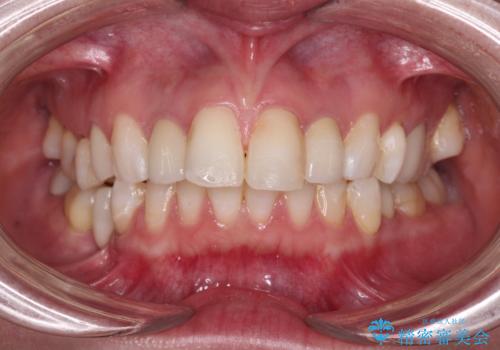

- クラウンから金属の土台が見えてきてしまったとのことで、作り替えを希望して来院された患者様です。

前歯や金属が露出している歯、痛みを感じる歯を中心に、オールセラミッククラウンにて補綴治療することとしました。

以前はセラミッククラウンのフレームとして金属が使用されており、歯肉の経年変化やセラミックのすり減りなどにより、金属が見えるようになってくることがあります。

現在は金属の代わりに強化セラミックを使用したオールセラミッククラウンが主流です。金属色が気になる方はご相談ください。